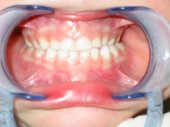

Una mordida cruzada anterior es el inicio visual

de una progenie mandibular. Sólo si se frena y corrige a una edad

temprana, que es cuando se originan, recupera de manera efectiva el desarrollo

normal.